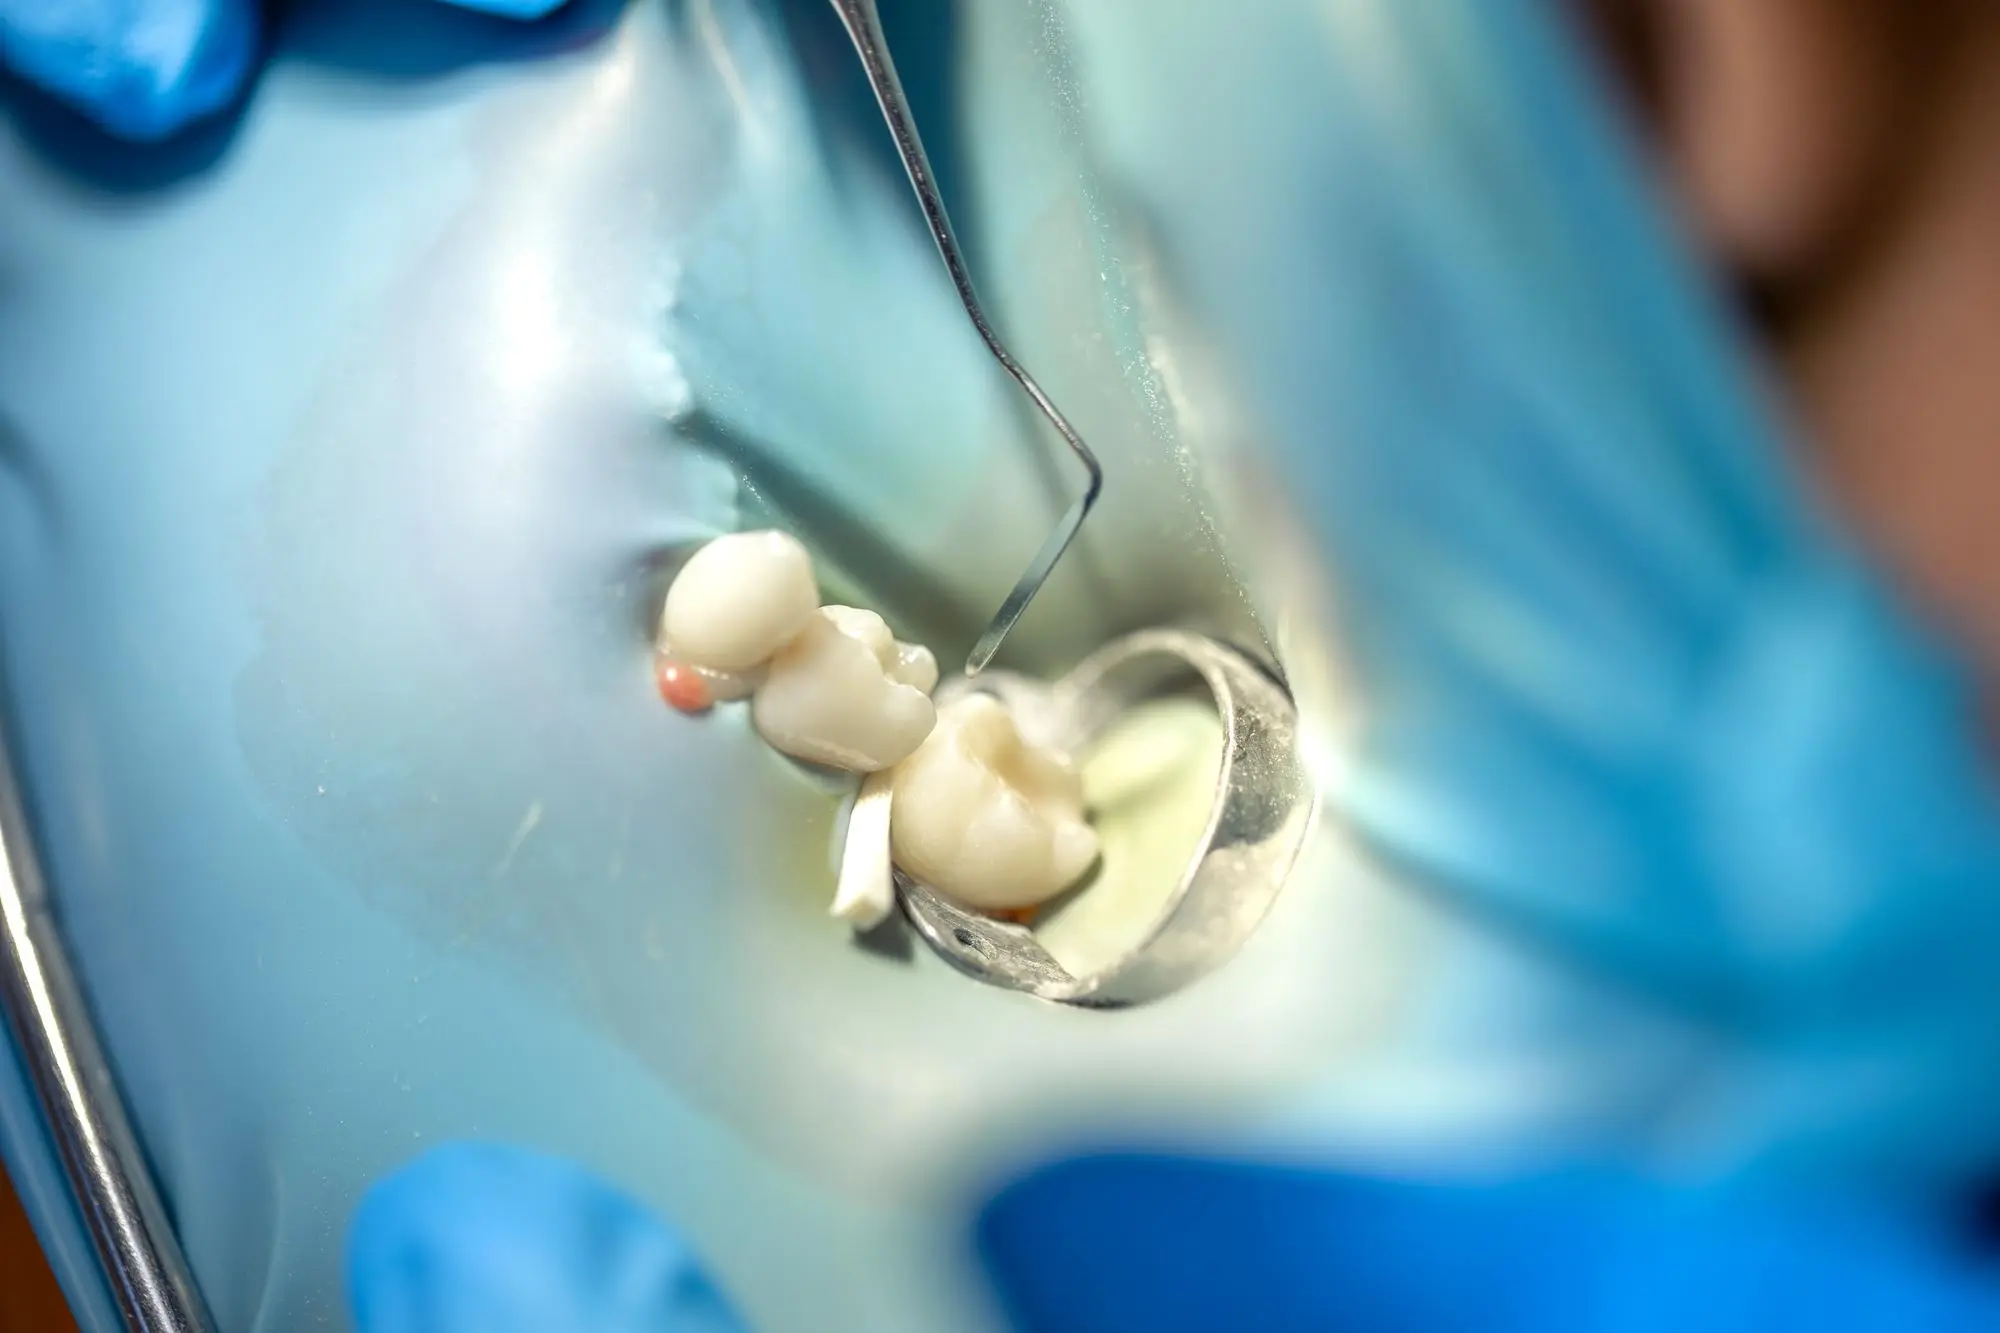

Extração do Siso

Extração do siso em Campo Grande - MS com planejamento e segurança para casos de dor, inflamação ou falta de espaço, priorizando conforto e boa recuperação.